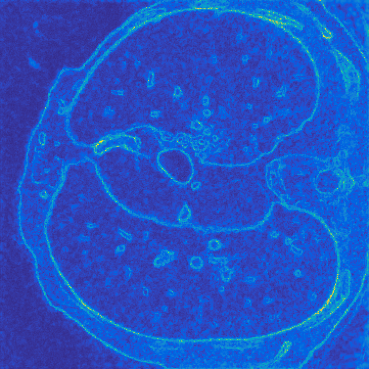

Deep learning-based image reconstruction approaches have demonstrated impressive empirical performance in many imaging modalities. These approaches generally require a large amount of high-quality training data, which is often not available. To circumvent this issue, we develop a novel unsupervised knowledge-transfer paradigm for learned iterative reconstruction within a Bayesian framework. The proposed approach learns an iterative reconstruction network in two phases. The first phase trains a reconstruction network with a set of ordered pairs comprising of ground truth images and measurement data. The second phase fine-tunes the pretrained network to the measurement data without supervision. Furthermore, the framework delivers uncertainty information over the reconstructed image. We present extensive experimental results on low-dose and sparse-view computed tomography, showing that the proposed framework significantly improves reconstruction quality not only visually, but also quantitatively in terms of PSNR and SSIM, and is competitive with several state-of-the-art supervised and unsupervised reconstruction techniques.